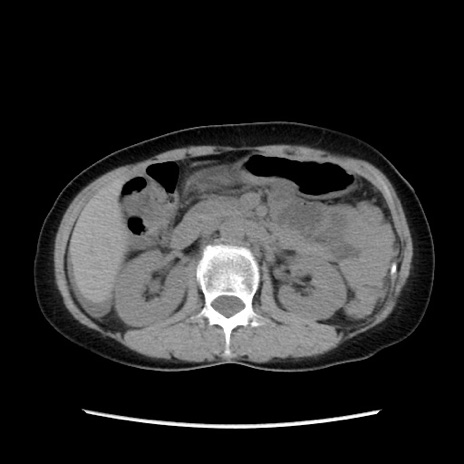

症例32(横断像)

【症例】40歳代 女性

【主訴】上腹部痛、嘔気・嘔吐

【現病歴】約9時間前頃から急に上腹部痛、嘔気、嘔吐が出現。改善しないため救急要請。

【既往歴】子宮頚癌(広汎子宮全摘術、放射線療法)、腸閉塞

【身体所見】腹部:平坦、軟、腸雑音亢進、上腹部を中心に腹部全体に圧痛あり。

【データ】WBC 8400、CRP 0.03